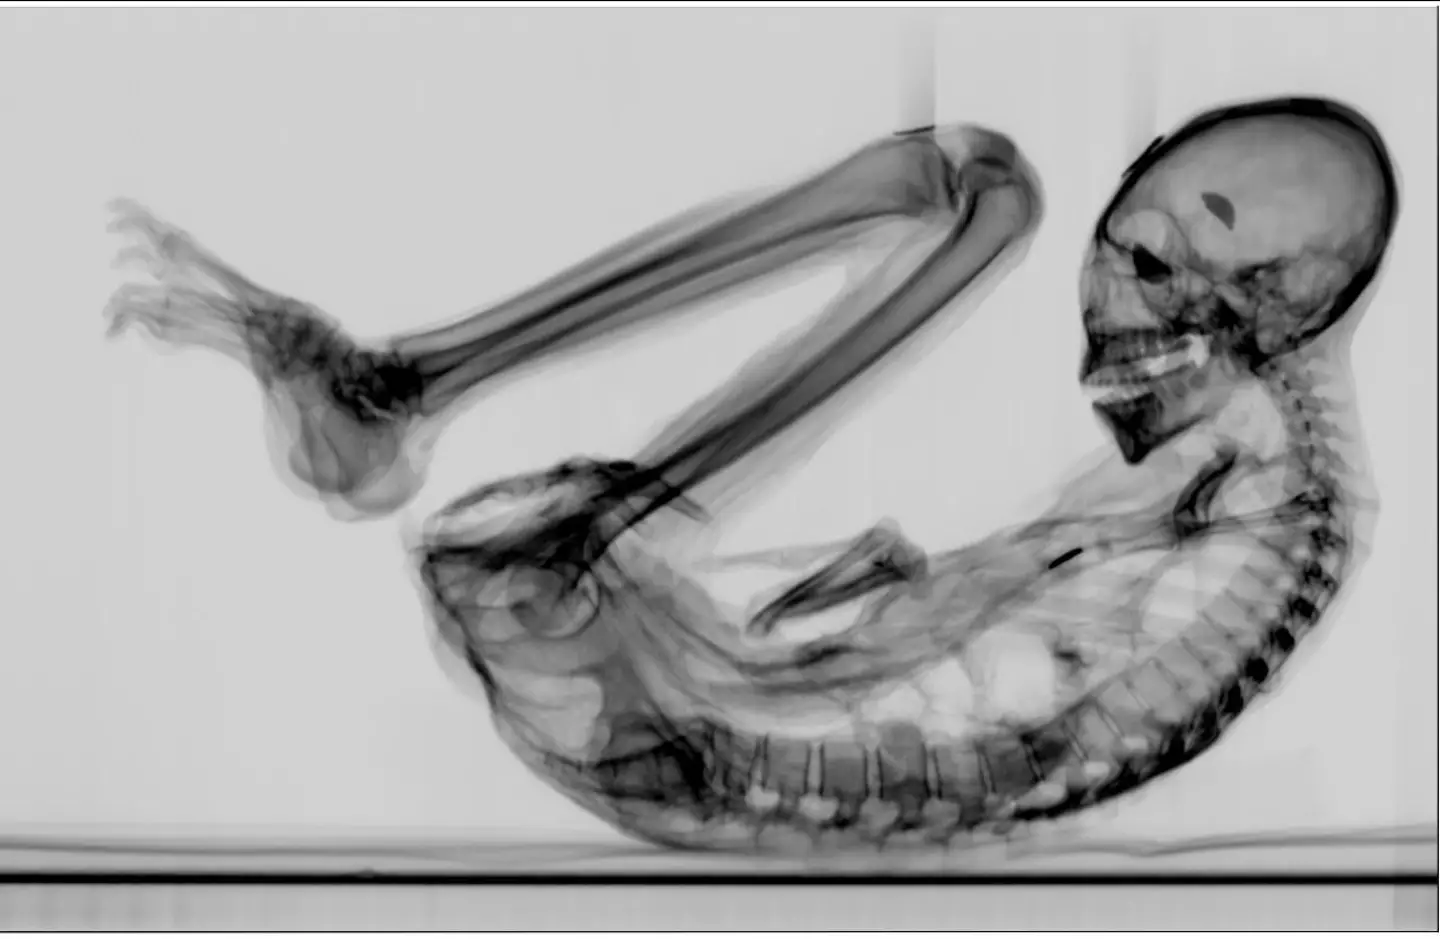

While analysing one of the mummified specimens, named Montserrat, scientists discovered what they describe as a fetus inside her womb. CT imaging showed a tiny body lying on its back with its head facing downwards and arms near the pelvic region, the classic foetal position.

Lead researcher Dr David Ruiz Vela, alongside journalist Jois Mantilla, carried out the scans at a radiology centre in Lima. According to their analysis, Montserrat was less than 30 weeks pregnant when she died, over a millennium ago.

The gestational age of the fetus was determined by the length of its femur, 43 millimetres, a common technique used in prenatal ultrasounds. Researchers noted that the bones were still soft and had not yet fully fused, a fact that likely contributed to visible distortions seen in the scan.

Digital reconstruction showed that the fetus’s face had rotated backwards, likely due to the mummification process and the soft, undeveloped state of its skull.